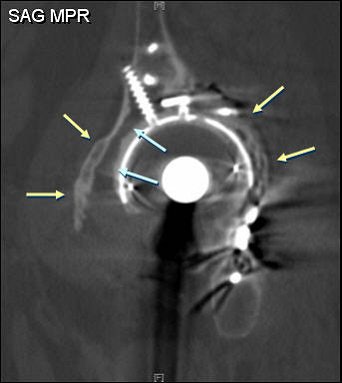

![]() |

| A 61-year-old woman with bilateral hip prostheses who was referred before surgery for evaluation of remaining "bone stock" surrounding cetabular hardware. Multislice CT was performed with thin slices (2.5-mm slice width, 1.4-mm reconstruction interval), high kilovoltage (140 kVp), and high tube current (750 mAs). Coronal reformatted image shows sparse amount of bone surrounding acetabular components (solid arrows). Wear of plastic joint liner of right hip (open arrow) is shown. Optimal scanning technique minimized metal artifacts. Buckwalter KA, Rydberg J, Kopecky KK, Crow K, Edward L, Yang EL, "Musculoskeletal Imaging with Multislice CT" (American Journal of Roentgenology, 2001; 176:979-986). |